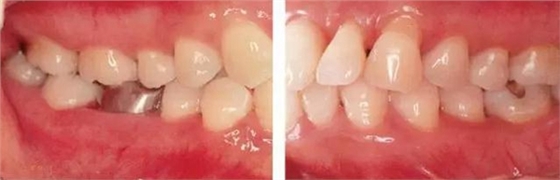

●參考病例① 35歲女性

35歲女性。妊娠4個(gè)月。過去雖然接受過刷牙指導(dǎo),但菌斑控制狀態(tài)依然不理想?;颊哂邪l(fā)現(xiàn)自己刷牙時(shí)牙齦出血。

●參考病例② 25歲女性

25歲女性。菌斑控制狀態(tài)不好。齦溝除磨牙處外全在3mm以下,X光照片上左上、右下、左下的第一磨牙上有垂直性骨吸收。這個(gè)病例是參考病例①10年前的狀態(tài),是典型的侵襲性牙周炎局部型。